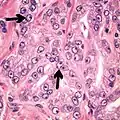

- Collagenous micronodules[4]

- Glomerulations,[4] epithelial proliferations into one or more gland lumina, typically a cribriform tuft with a single attachment to the gland wall.[18]

Glomerulation.